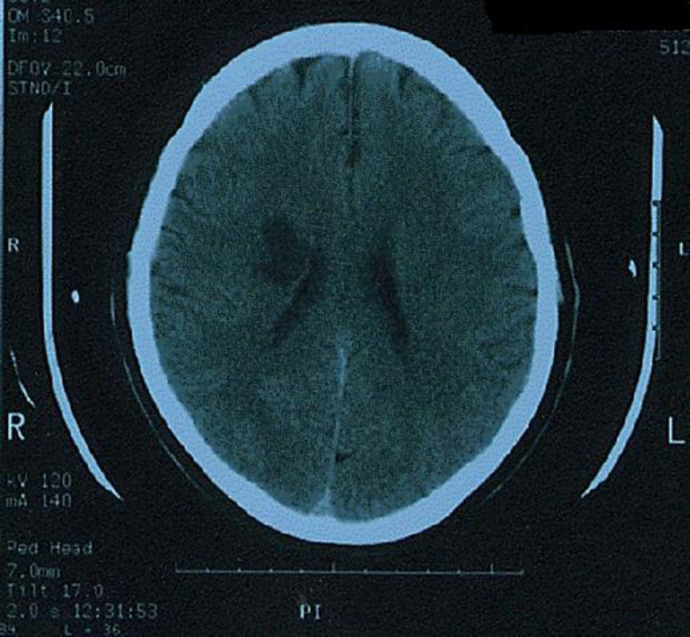

Computed tomography scan of the brain showed an area of infarction over the right subcortical corona radiata region (Fig. 1). He received inpatient stroke care and then was discharged home.

Fig. 1.

Computed tomography scan of the brain axial cuts showing a well-demarcated hypodense lesion consistent with ischemic infarction on the right centrum semiovale.